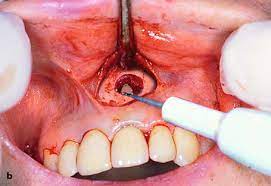

tooth During the procedure, your dentist or endodontist cuts through your gum and pushes the gum tissue aside in order to reach the root. Usually just a few millimeters of the root are removed, as is any infected tissue surrounding the root.

tooth After the root tip is removed, the root canal inside the tooth is cleaned and sealed with a small filling to prevent future infection. Your dentist or endodontist may then take another X-ray to make sure your tooth and jaw look good and that there are no spaces where a new infection could take hold.